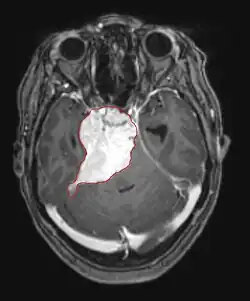

Hirnmetastasen

Hirnmetastasen sind die häufigsten intrakraniellen Neoplasien bei Erwachsenen, die zehnmal häufiger vorkommen als primäre Hirntumoren. Sie treten bei 20 bis 40 Prozent der krebskranken Erwachsenen auf und sind hauptsächlich mit Lungen- und Brustkrebs sowie Melanomen assoziiert. Diese Läsionen sind das Ergebnis der Ausbreitung von Krebszellen durch den Blutkreislauf und treten am häufigsten an der Verbindung der grauen mit der weißen Substanz auf, wo sich der Querschnitt der Blutgefäße ändert und damit Tumorzellembolien eingeschlossen werden. 80 Prozent der Läsionen treten in den Gehirnhälften auf, 15 Prozent im Kleinhirn und 5 Prozent im Hirnstamm. Ungefähr 80 Prozent der Patienten haben eine Anamnese von systemischem Krebs und 70 Prozent haben multiple Hirnmetastasen.

Bei Diagnose und Behandlung dieser Läsionen wurden in jüngster Zeit erhebliche Fortschritte erzielt, wodurch das Überleben und die Kontrolle der Symptomatik verbessert wurden. Das Auftreten von Anzeichen und Symptomen ähnelt denen anderer massiver Läsionen im Gehirn. Das Diagnoseverfahren der Wahl ist die Kernspintomographie unter Verwendung von Kontrastmitteln.